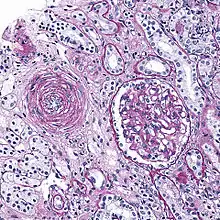

Micrograph showing hyaline arteriolosclerosis in the kidney. PAS stain.

Also arterial hyalinosis and arteriolar hyalinosis refers to thickening of the walls of arterioles by the deposits that appear as homogeneous pink hyaline material in routine staining.[3] It is a type of arteriolosclerosis, which refers to thickening of the arteriolar wall and is part of the ageing process.[4]

Lesions reflect leakage of plasma components across vascular endothelium and excessive extracellular matrix production by smooth muscle cells, usually secondary to hypertension.[7] Hyaline arteriolosclerosis is a major morphologic characteristic of benign nephrosclerosis, in which the arteriolar narrowing causes diffuse impairment of renal blood supply, with loss of nephrons.[5] The narrowing of the lumen can decrease renal blood flow and hence glomerular filtration rate leading to increased renin secretion and a perpetuating cycle with increasing blood pressure and decreasing kidney function.